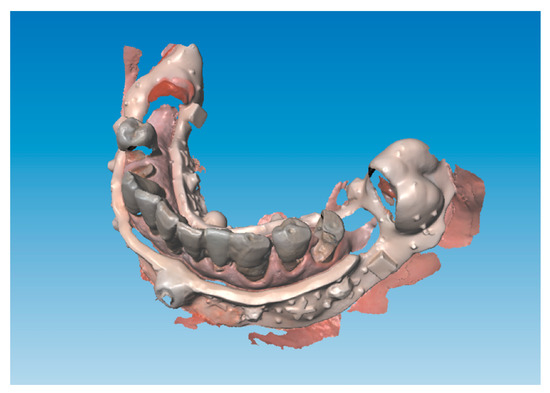

This technique allows one to change the vertical dimension of occlusion before the actual surgery using for example direct composite restorations on the existing dentition if present to test the desired vertical dimension changes for any clinical purpose (gnathological issues, collapsed vertical dimension and so forth). It is also possible to immediately determine an increase or any other kind of change in the maxilla–mandibular relationship using conventional techniques before digitally recording it. An example is the digital recording of the maxilla–mandibular relationship in the centric relation using an occlusal wax. In the case of a reduced number of occluding teeth proper stabilization of the maxilla–mandibular position into the centric relation is required using conventional methods before digitally recording the determined position by scanning. The described case did not require any change to the existing occlusal determinants. The next step consisted of the design of the lower acrylic resin jig, which is the digital index, on the preliminary lower impression (Figure 4) to superimpose the lower presurgical scan with the postsurgical impression.

This digital index (Figure 5) was to be stabilized by three support points to ensure a reliable position in relation to the lower jaw. It is important to achieve stability of the index and to avoid undercuts that are retentive areas. After the 3D printing process was finished and supports were removed from the index, it was placed over the 3D-printed lower model (Figure 4D) and the sleeve for the anterior median pin was placed in a position that could not impair the placement of the implants during surgery. This step did not require much programming and was performed by hand on the model since in this particular case and in any full arch mandibular restorative treatment it is preferable in accordance with plenty of scientific evidence [13] to reduce the number of implants supporting full-arch rehabilitations, thus leaving plenty of space in the anterior mandibular alveolar bone to place our median pin in an area without damaging anatomical structures nor impairing potential implant sites. There is no issue regarding where to place the sleeve for the pin because the presurgical scan is taken immediately prior to surgery and the postoperative scan is taken just after surgery thus allowing one to place the pin in the exact same hole performed during the presurgical scan. There is no need to place in a particular place in the preoperative scan since the latter represents the reference for the second one, the only issue is to have the pin positioned in the same spot in both scans as explained above. Regarding the distal support points as one may notice in Figure 4D it is possible to improve precision by relying the occlusal rests of the resin index with some Duralay (Reliance Dental, Worth, IL) to improve the fitting between the digital index and the occlusal rest seats of supporting posterior teeth.

If the existing dentition lacks one or more distal teeth that can be maintained even after surgery (second and third lower molars) to be used as support points, one or more anchor pins should be used instead to provide sufficient stability for the digital index. A median anterior anchor pin is always needed to provide anterior stability. Geometrical patterns are to be included in the digital index in order to provide sufficient reference points to superimpose preoperative and postoperative impressions. In this patient only the anterior pin was needed.

Extraction of all teeth was performed apart from the lower second molars that did not impair implant placement and served as distal support points for the digital index. Implants were inserted and scan abutments and the lower digital index was placed to take the postoperative digital impressions (Figure 7).

Figure 4. Design of the lower acrylic resin jig. (A) The digital lower scan is imported into Autodesk Meshmixer (Autodesk Inc., San Rafael, CA, USA) to design the digital index which will later serve to superimpose mandibular preoperative and postoperative scans. (B) The inferior digital index is designed in order to obtain stability thus proving occlusal clearance on all teeth but the lower second molars and providing the space for a frontal median stabilization pin. (C) Cubic and tetrahedral reference points are positioned to ease the match between the preoperative and the postoperative scan. (D) The digital index was printed using a monochromatic LCD 3D printer (Liquid Crystal Precision 1.5, Photocentric, Phoenix, AZ, USA) with XY resolution equal to 47 µm and Anycubic Dental Non-Castable UV Resin (Anycubic Shenzhen, Guangdong, China). In the picture it can be seen on the lower 3D printed model (Form 3B, Somerville, MA, USA) that was printed using Gray Model Resin (Form 3B, Somerville, MA, USA) with the same printing resolution. The guided anchor pin sleeve (Nobel Biocare AB, Gothenburg, Sweden) was secondarily fixed with the dental composite in the anterior hole left for this purpose in Mesh Mixer computer aided design (see Figure C).